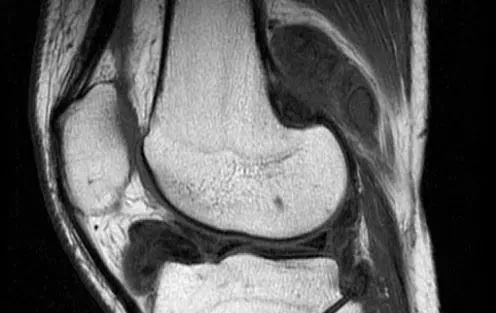

弹响低钝且频仍,响声发自骨外侧的髌股关节,同时伴关节肿胀,偶有交锁征象。MRI可看到关节退变,半月板呈“孤岛样”。关节镜下可看到关节软骨及半月板退变、骨质增生压迫韧带和关节囊。

病因不明,外伤时可诱发。弹响低钝,位置不确定,频率低,膝关节压痛弥散,伴关节肿胀,交锁少见。MRI可看到滑膜增生,呈结节状。关节镜下可看到滑膜充血增生,含铁血黄素沉积,侵蚀关节软骨和韧带。

外伤引起。膝关节不稳导致弹响,频率低且低钝,可伴有交锁,抽屉试验阳性。核磁可明晰诊断。关节镜下可看到韧带断端嵌于关节间隙,或有软骨损伤。